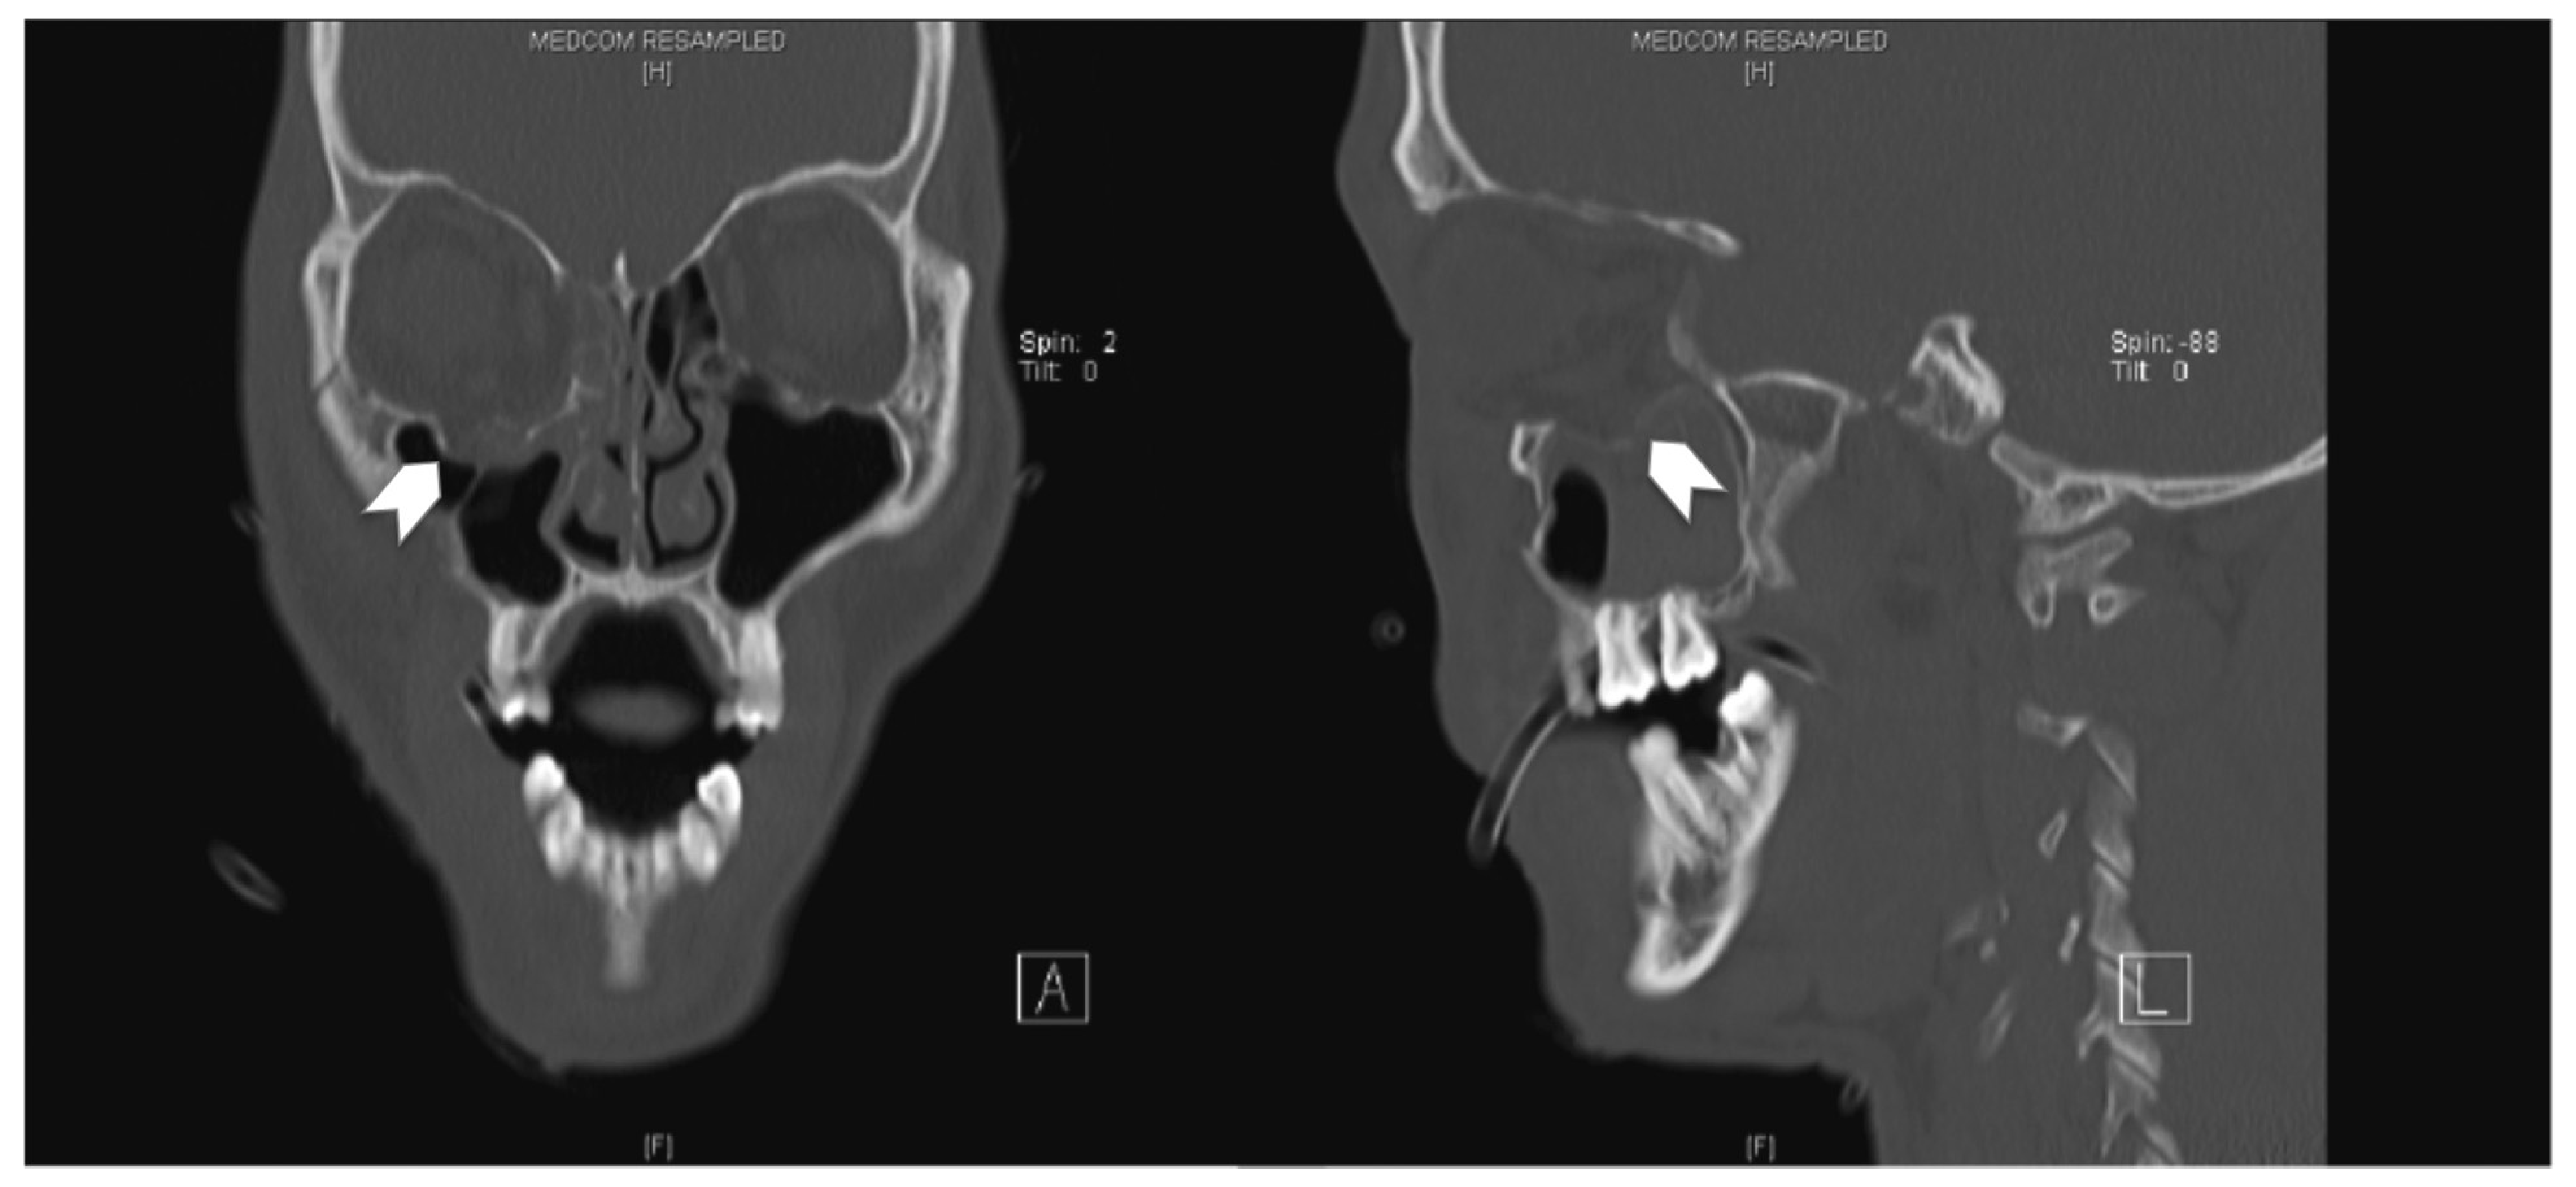

A 66-year-old woman sustained a left ZMC fracture and orbital floor fracture following a fall (Figure 5), resulting in left enophthalmos and diplopia on upward gaze. She underwent ORIF and orbital floor reconstruction 12 days after the injury. Both the 0.4-mm titanium orbital mesh and orbital rim plate were used (Figure 6). Postoperatively, she complained of progressive worsening of left upward gaze diplopia, starting around 2 weeks postoperatively and worsening over 4 weeks. There was also dimpling noted over the left lower lid due to lid retraction; however, forced-duction test was negative. She was given lower eyelid scar massage, which was performed in an upward oblique fashion from medial to lateral, and steroid injections (8 IU of triamcinolone) into the lower eyelid. On the 9th week postoperative follow-up, she reported improvement of diplopia but still had lower eyelid retraction and a tugging sensation (Figure 7). She was then given 0.3 mL of hyaluronic acid (HA) filler (Restylane; Galderma, Lausanne, Switzerland) into the posterior lamella space to correct the lower eyelid retraction. She experienced immediate and sustained (at 1 month) relief of symptoms of tugging and eyelid retraction.

Figure 6. Coronal and sagittal cuts of the postoperative CT scan of the face (Case 2) demonstrating reduction of all periorbita. Although the posterior edge of the plate is slightly depressed, there is no tethering of the inferior rectus muscle.

Figure 7. At 9-week postoperation. Left—left lower lid dimpling on primary gaze; right—no tethering of inferior rectus and inferior oblique muscles.